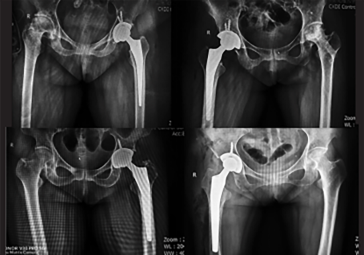

· 髖關(guān)節(jié)置換:髖臼+股骨雙側(cè)規(guī)劃

· 制定詳細(xì)植入計(jì)劃,術(shù)前預(yù)演